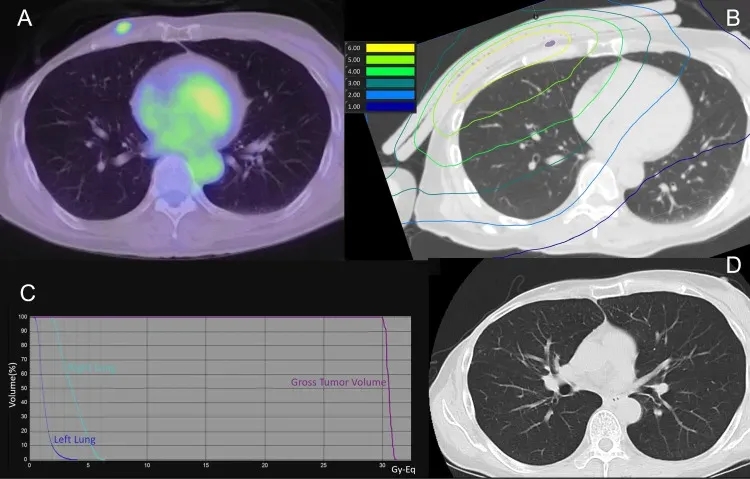

《Cureus》曾报道全球首个采用基于加速器的BNCT系统,治疗放疗后复发性乳腺癌的临床研究。其中一例52岁女性患者的治疗经历颇具参考价值:该患者10年前因右侧乳腺癌,先后接受化疗、保乳手术及25次共50Gy的保乳放疗;3年半前疾病局部复发,接受手术(rpT3N2M0)及化疗;后续虽又经历两次局部复发手术及激素治疗,癌症仍再次复发,最终接受BNCT治疗。

结果显示:在BNCT治疗后1天、7天、30天、60天、90天的CT扫描中,均未发现放射性肺炎迹象。下图3为该患者的肺部剂量分布及治疗后90天的CT扫描影像。

好消息是,日本近期已启动硼中子俘获疗法的临床研究,入组人群仅限不可切除的局部晚期或局部复发的头颈癌、乳腺癌成年患者等。感兴趣的癌友可将治疗经历、近期影像及病理学检查结果,提交至医学部,进行初步评估或了解详细入排标准。